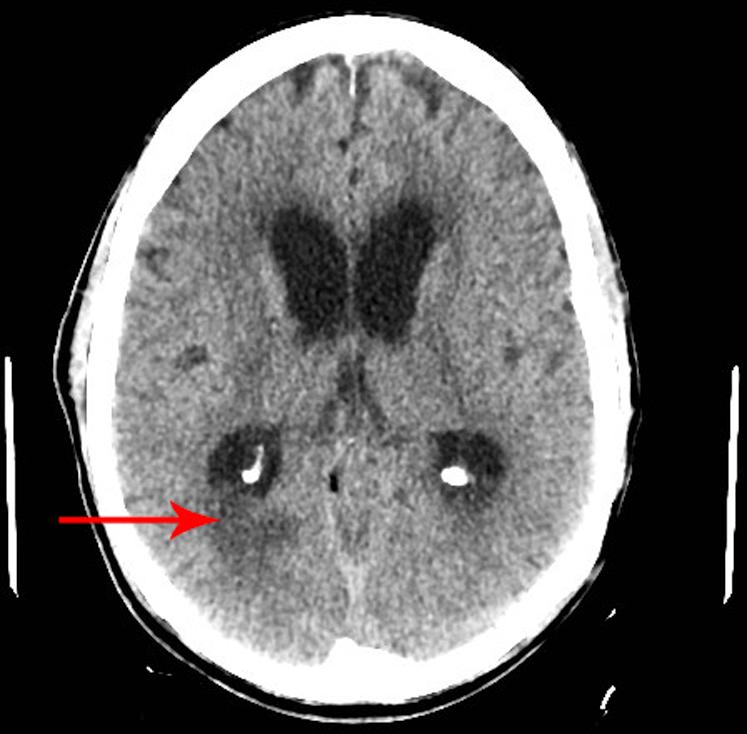

A 66-year-old male with a history of hypertension, back pain, diverticulosis and anal fistula presents with acute onset syncopal episodes, worsening back pain, and altered mental status. The patient exhibited considerable leukocytosis but was hemodynamically stable. CT imaging of the head revealed a gas pattern in the posterior fossa and velum interpositum. CT imaging of the abdomen and pelvis revealed a needle-like foreign body traversing the left sacrum to the sigmoid colon. A lumbar puncture revealed meningitis. Flexible sigmoidoscopies were performed without successful visualization of the foreign body. An explorative laparoscopy was successfully performed, enabling retrieval of what was determined to be a wooden toothpick. The patient remained hemodynamically stable with persistent altered mental status and was eventually discharged after completion of antibiotics on day 47 of hospitalization. This case illustrates a rare complication of ingesting a sharp foreign body that was identified by CT of the brain and abdomen/pelvis with successful surgical repair.

一名66岁男性,有高血压、背痛、憩室病和肛瘘病史,现出现急性发作的晕厥、背痛加重及精神状态改变。患者白细胞显著增多,但血流动力学稳定。头部CT成像显示后颅窝和中间帆有气体影。腹部和盆腔CT成像显示一个针状异物穿过左骶骨至乙状结肠。腰椎穿刺显示为脑膜炎。进行了乙状结肠镜检查,但未成功看到异物。成功进行了探索性腹腔镜检查,取出了一根木质牙签。患者血流动力学稳定,但精神状态持续改变,住院第47天完成抗生素治疗后最终出院。该病例说明了摄入尖锐异物的一种罕见并发症,通过脑部及腹部/盆腔CT得以确诊,并成功进行了手术修复。